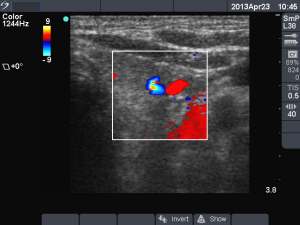

Second session (second row of images):

Clinical presentation: the patient became aware of mild neck discomfort lasting for 2 days.

I removed 3.5 ml serous-watery fluid and administered 1.5 mL ethanol.